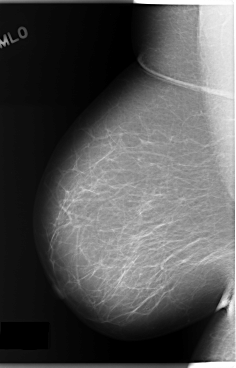

C_0132_1.RIGHT_MLO

RIGHT_CC LINES 5888 PIXELS_PER_LINE 3512 BITS_PER_PIXEL 12 RESOLUTION 50 NON_OVERLAY

RIGHT_MLO LINES 5880 PIXELS_PER_LINE 3768 BITS_PER_PIXEL 12 RESOLUTION 50 NON_OVERLAY